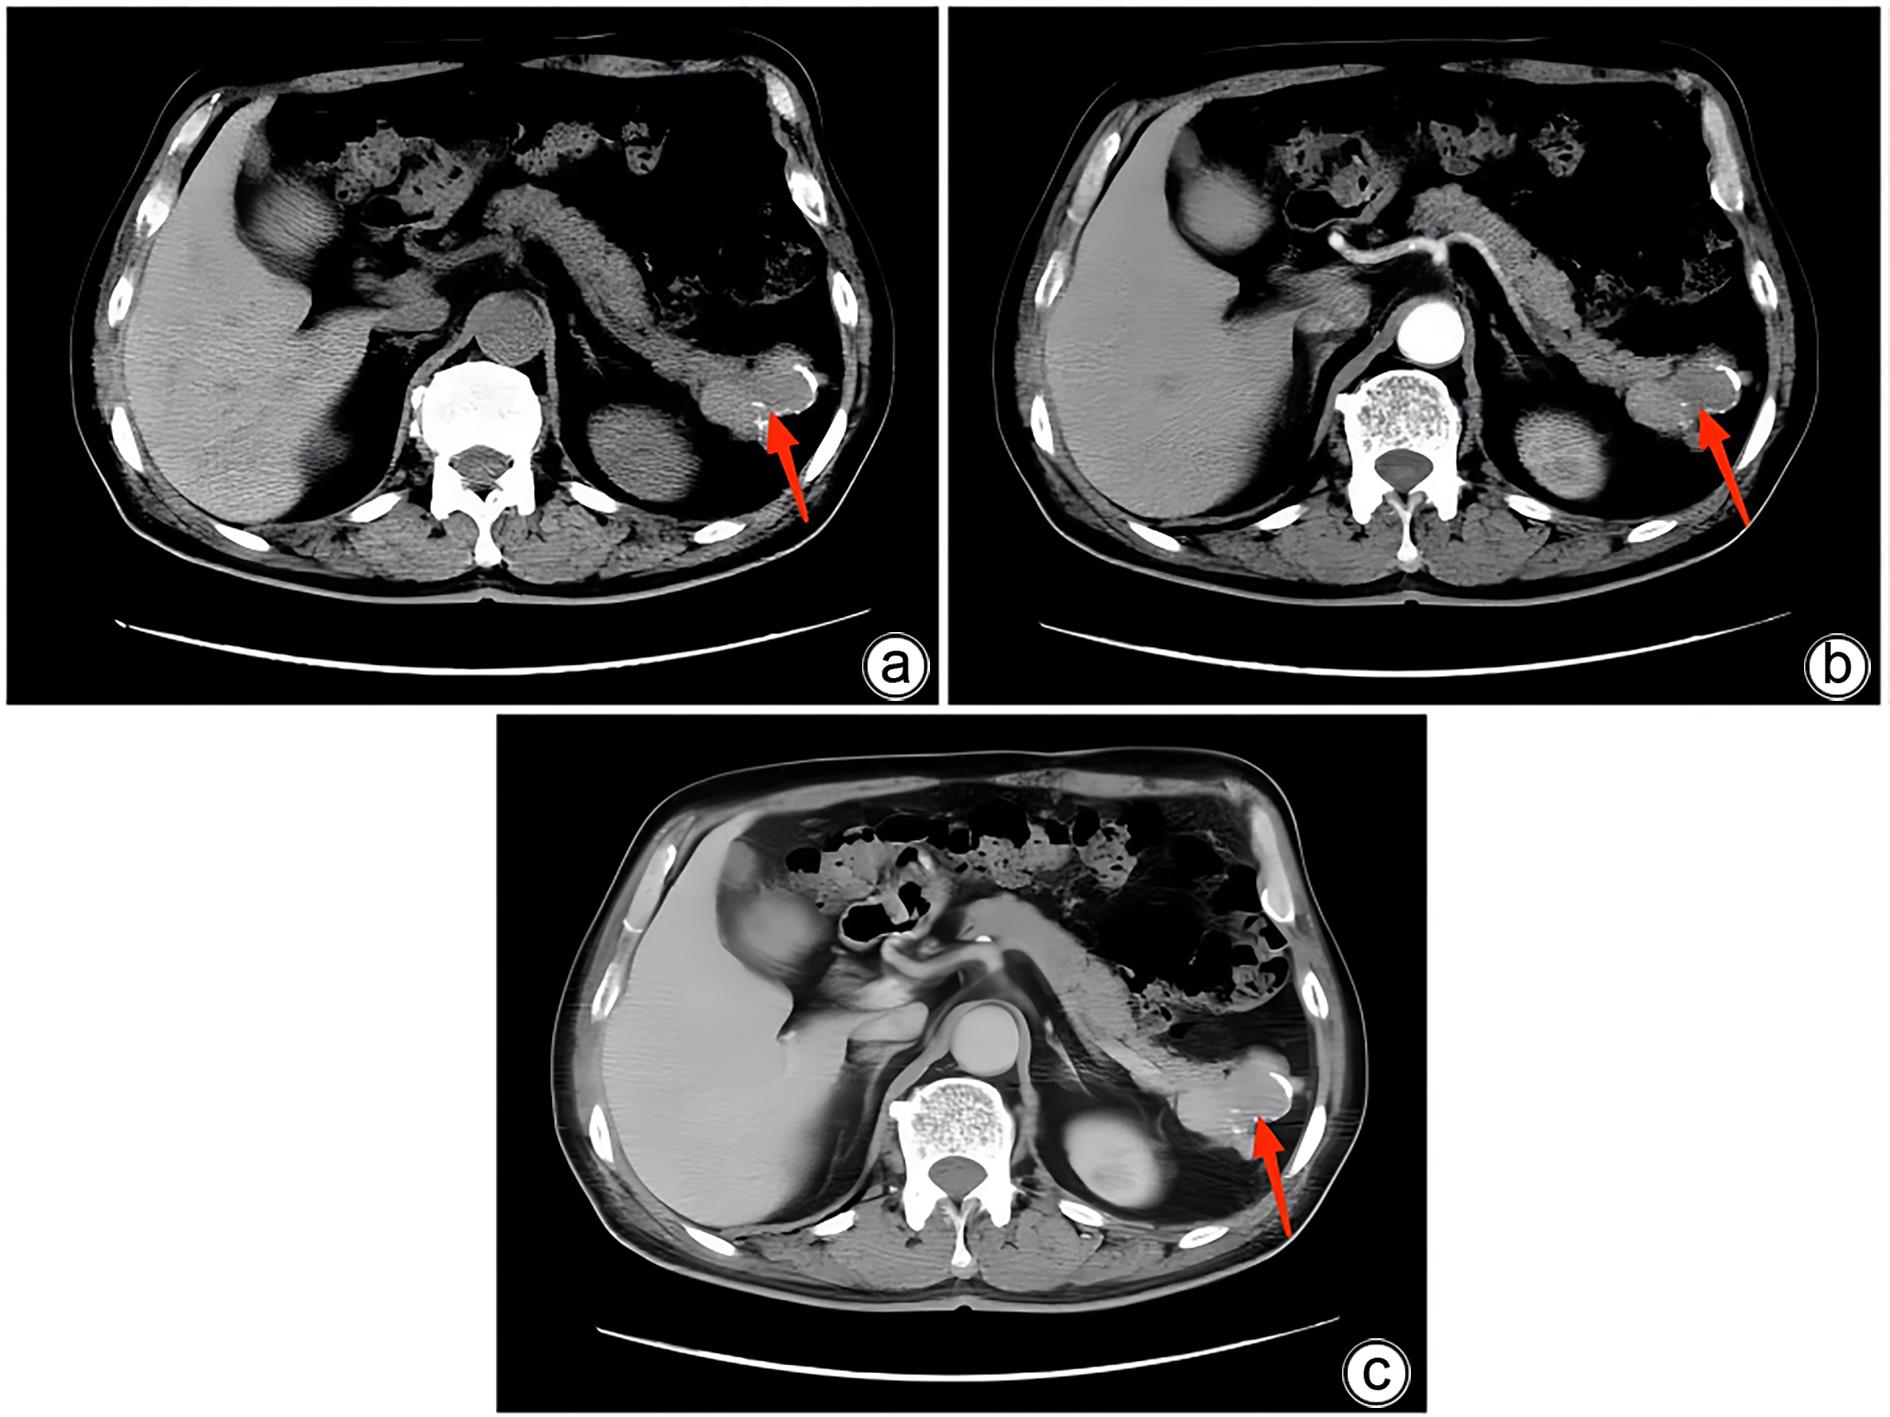

Misdiagnosis of intrapancreatic accessory spleen: A report of two cases

Mengzhe ZHANG, Jie RAO, Zhengle ZHANG

2024, 40(2): 365-368. DOI: 10.12449/JCH240223

Abstract(1384) HTML (333) PDF (1188KB)(176)

Abstract:

Accessory spleen refers to the spleen tissue that exists outside of the normal spleen, with a similar structure to the main spleen and certain functions. Intrapancreatic accessory spleen (IPAS) completely enveloped by the pancreas has an incidence rate of only 2%, and it is easily misdiagnosed in clinical practice due to its atypical clinical symptoms and similar radiological features to pancreatic neuroendocrine tumor, pancreatic solid pseudopapillary tumor, and other pancreatic space-occupying lesions. This article reports the clinical data of two patients with IPAS who were misdiagnosed as pancreatic neuroendocrine tumor and pancreatic solid pseudopapillary tumor, respectively, analyzes the reasons for misdiagnosis, and summarizes the experience in diagnosis and treatment, in order to improve the ability for the differential diagnosis of IPAS in clinical practice.